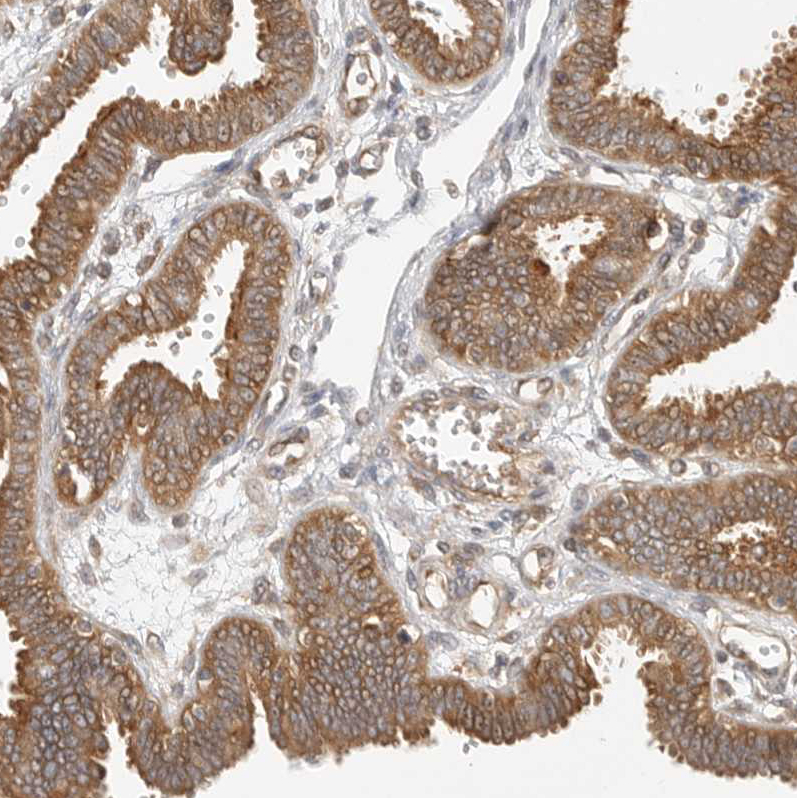

Immunohistochemical staining of human small intestine shows strong cytoplasmic positivity in glandular cells.